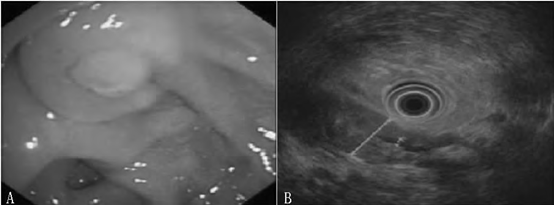

以下为胃镜和超声胃镜检查结果:

注: A 为胃镜,示慢性浅表性胃炎,十二指肠球部息肉; B 为超声胃镜,示胰腺回声增粗,胰管呈串珠状扩张

胃镜和超声胃镜检查结果

胃镜检查示慢性浅表性胃炎,十二指肠球部息肉。结肠镜检查示结肠多发息肉。超声胃镜检查示胰头、胰体回声增粗,呈混合回声改变,内可见高回声斑点,胰头厚约2.6 cm,胰管未见扩张,直径约2.0mm; 胰尾回声增粗,胰管呈串珠状扩张,直径约3 mm; 胆总管未见扩张,直径约5mm; 胰腺周围及贲门部腹主动脉旁未见肿大淋巴结。